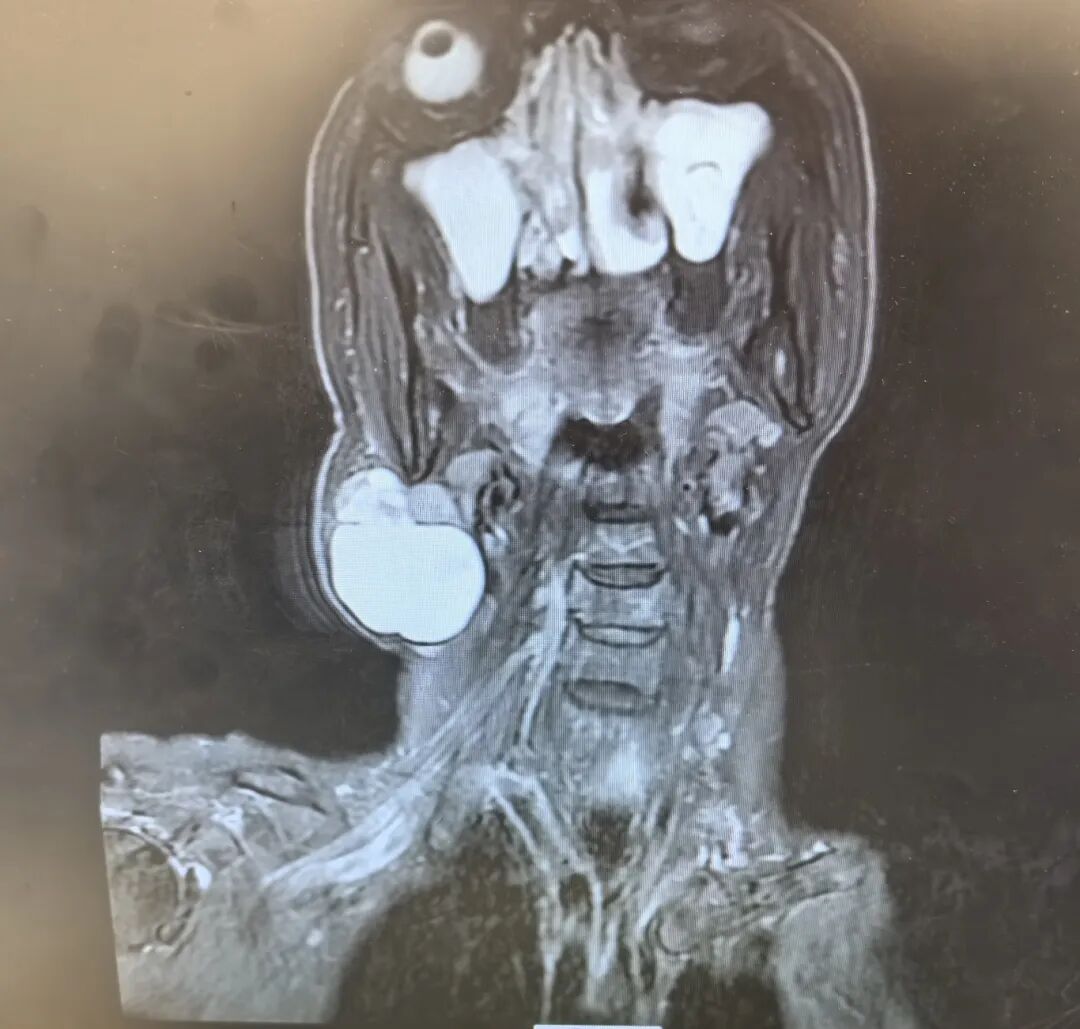

门诊接诊的李莹医生对韩女士进行了详细询问病史,并完善了核磁等相关检查。结合影像学结果与临床评估,李莹医生以“右侧腮腺区肿物”将韩女士收治入院。随后,龚龙岗主任、马戈主任医师带领团队对患者的病情展开了全面研判。考虑到肿物体积较大且生长特性特殊,为确保手术的彻底性,并最大程度保护面神经功能,团队最终确定实施“右侧颈部肿物切除术 + 右侧腮腺部分切除术 + 面神经松解术”。

手术过程中,团队成员们全神贯注、精细操作。他们小心地剥离肿物,同时精准解剖面神经,有效规避了术后面瘫等并发症风险,成功完整地切除了病灶。术后病理检查结果确诊肿物为“多形性腺瘤”,这是一种唾液腺常见的良性肿瘤,虽然恶变概率较低,但存在“缓慢生长后突然加速”的特性,韩女士的病情正符合这一典型表现。